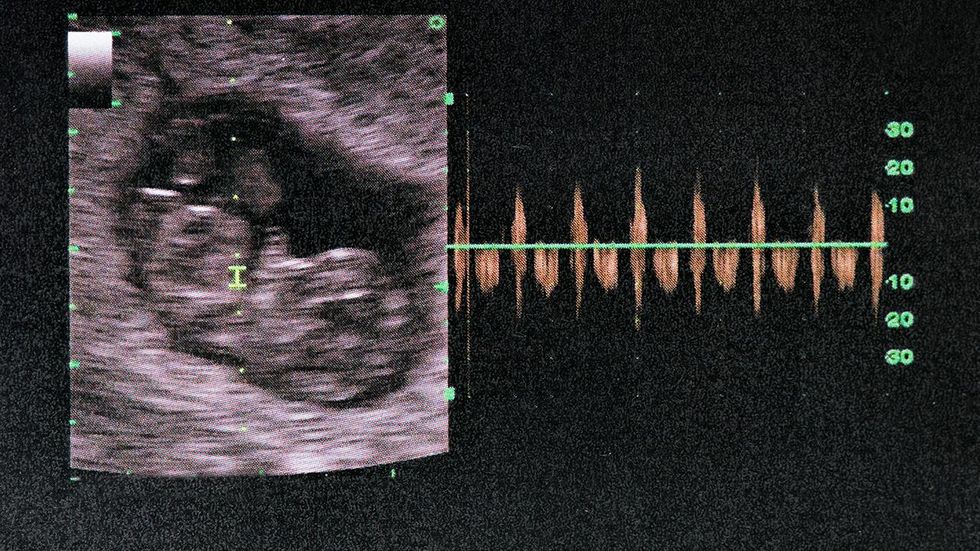

Mississippi lawmakers are considering a bill to ban most abortions after 15 weeks. The image here shows a fetus at 24 weeks. (ISMODE/Getty Images)